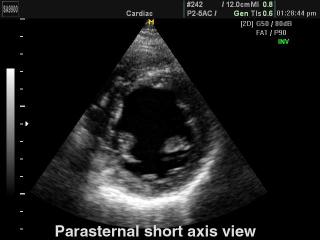

Heart (short axis of LV), B-mode

SonoAce-9900. Heart (short axis of LV), B-mode.